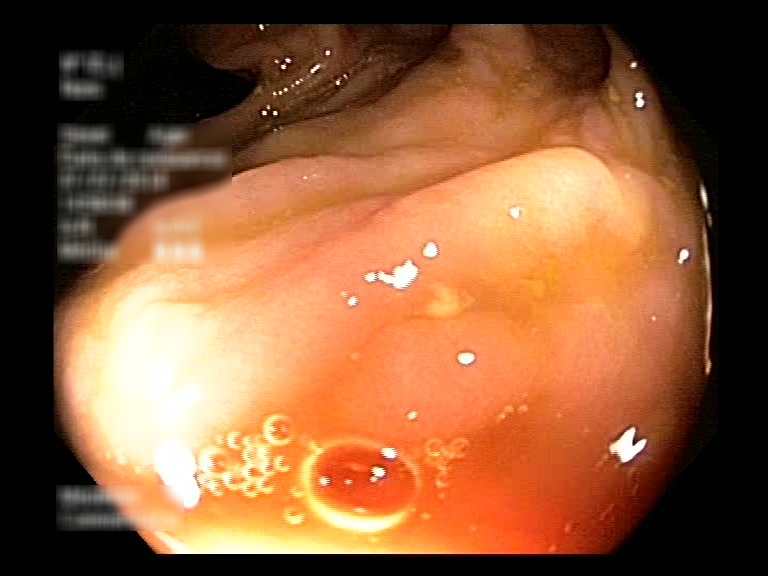

| Lesion | White Light Frame | NBI Frame | White Light Video | NBI Video | Camera Calibration |

| serrated_01 |  |

|

WL.mp4 | NBI.mp4 | cam.xml |